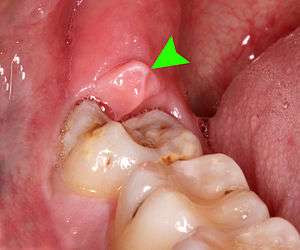

When wisdom teeth communicate with the mouth, the most common symptom is localized pain, swelling and bleeding of the tissue overlying the tooth. This tissue is called the operculum and the disorder called pericoronitis which means inflammation around the crown of the tooth.[3]:141 Low grade chronic periodontitis commonly occurs on either the wisdom tooth or the second molar, causing less obvious symptoms such as bad breath and bleeding from the gums. The teeth can also remain asymptomatic (pain free), even with disease.[5] As the teeth near the mouth during normal development, people sometimes report mild pressure of other symptoms similar to teething.